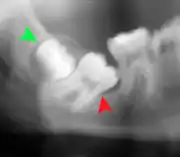

Impacted wisdom tooth with a backward tilt (distoangular impaction) and chronic infection to back of crown (green arrow)

Pericoronitis (green arrow) in lower right wisdom tooth

Impacted wisdom teeth without communication to the mouth, that have no pathology associated with the tooth, and have not caused tooth resorption on the blocking tooth, rarely have symptoms.[11] The chances of developing pathology on an impacted wisdom tooth that is not communicating with the mouth is approximately 12%.[11] However, when impacted wisdom teeth communicate with the mouth, food and bacteria penetrate to the space around the tooth and cause symptoms such as localized pain, swelling and bleeding of the tissue overlying the tooth. The tissue overlying the tooth is called the operculum, and the disorder is called pericoronitis which means inflammation around the crown of the tooth.[5]:141 Low grade chronic periodontitis commonly occurs on either the wisdom tooth or the second molar, causing less obvious symptoms such as bad breath and bleeding from the gums. The teeth can also remain asymptomatic (pain free), even with disease.[7]